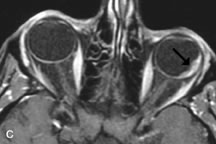

Metastatic Tumors

Breast carcinoma metastatic to the orbit has been demonstrated to be hypointense to the surrounding orbital fat on T1-weighted studies and hyperintense on T2-weighted images and has an affinity to the extraocular muscles (Fig. 20).50,64 The MRI characteristics of prostate carcinoma metastatic to the orbit have been described as involving the greater and lesser wing of the sphenoid, orbital roof, and optic canal. Diffuse bone hypertrophy with isointense or slightly hyperintense tissue on T1-weighted images represents the osteoblastic carcinomatous bone infiltration. Contrast enhancement is variable on T1-weighted and fat-suppressed images.65

Fig. 20. A. T1-weighted MR scan demonstrates nodular enlargement of both medial rectus muscles (arrows). B. T1-weighted fat-suppressed contrast-enhanced scan confirms the presence of small metnstatic deposits within the muscles (open arrows).